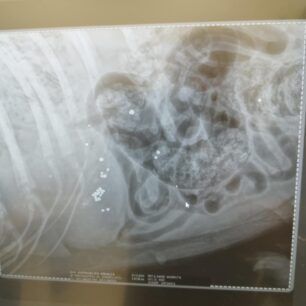

Τελικά οι ακτινογραφίες έδειξαν τι έχει συμβεί. Ο σκύλος είναι πυροβολημένο. Δεκάδες σκάγια εντοπίστηκαν στο σώμα του, στην σπονδυλική στήλη με αποτέλεσμα το ζώο να μην μπορεί όχι μόνο να κινηθεί αλλά και να αφοδεύσει με αποτέλεσμα στο έντερο να έχουν συσσωρευθεί κόπρανα.

Η Ευτυχία Πουρνάρα με αφορμή το περιστατικό επισήμανε τα εξής στις 3 Ιανουαρίου: «ΦΙΛΟΙ ΜΟΥ ΒΟΗΘΗΣΤΕ ΑΥΤΟ ΤΟ ΠΛΑΣΜΑ ΝΑ ΓΙΝΕΙ ΚΑΛΑ ΓΙΑΤΙ ΕΝΩ ΜΟΥ ΕΙΠΑΝ ΠΡΕΠΕΙ ΝΑ ΤΟ ΧΤΥΠΗΣΕ ΑΥΤΟΚΙΝΗΤΟ  ΣΥΓΚΛΟΝΙΣΤΙΚΑ ΟΤΑΝ ΟΙ ΑΚΤΙΝΟΓΡΑΦΙΕΣ ΔΕΙΞΑΝ ΟΤΙ ΤΟ ΚΟΡΜΑΚΙ ΤΟΥ ΣΚΥΛΑΚΟΥ ΕΙΤΑΝ ΓΕΜΑΤΟ ΣΚΑΓΙΑ ΔΙΑΣΠΟΡΑΣ ΕΝΑ ΤΟ ΒΡΕΙΚΕ ΣΤΗΝ ΣΠΟΝΔΥΛΙΚΗ ΣΤΥΛΗ Ο ΓΙΑΤΡΟΣ ΜΟΥ ΚΥΡΙΟΣ ΚΑΡΑΜΗΤΡΟΣ ΜΟΥ ΕΔΩΣΕ ΑΓΩΓΗ  ΤΟ ΖΩΟ ΔΕΝ ΜΠΟΡΟΥΣΕ ΝΑ ΑΦΟΔΕΥΣΗ ΚΑΙ ΠΡΙΣΤΗΚΕ ΚΑΝΟΥΜΕ ΑΓΩΝΑ ΝΑ ΤΟ ΒΟΗΘΗΣΟΥΜΕ ΤΟ ΚΑΛΟ ΕΙΝΑΙ ΟΤΙ ΑΙΣΘΑΝΕΤΑΙ ΤΑ ΠΟΔΑΡΑΚΙΑ ΤΟΥ ΘΑ ΣΑΣ ΠΩ ΝΕΟΤΕΡΑ ΤΟ ΚΑΘΑΡΜΑ ΠΟΥ ΤΟ ΠΥΡΟΒΟΛΗΣΕ  ΕΥΧΩΜΕ ΑΥΤΟ ΠΟΥ ΕΚΑΝΕ ΝΑ ΤΟ ΒΡΕΙ ΜΠΡΟΣΤΑ ΤΟΥ ΜΗΝ ΞΕΧΝΑΤΕ ΒΟΗΘΗΣΤΕ  ΕΧΩ ΑΓΩΝΑ ΜΠΡΟΣΤΑ ΜΟΥ ΓΙΑ ΝΑ ΣΩΘΕΙ ΣΤΕΙΛΤΕ ΜΗΝΝΥΜΑ ΣΤΟ ΜΕΣΣΕΝΤΖΕΡ  ΕΥΧΑΡΙΣΤΩ ΠΟΛΥ ΤΗΛ 6946348888 ΚΙΛΚΙΣ».